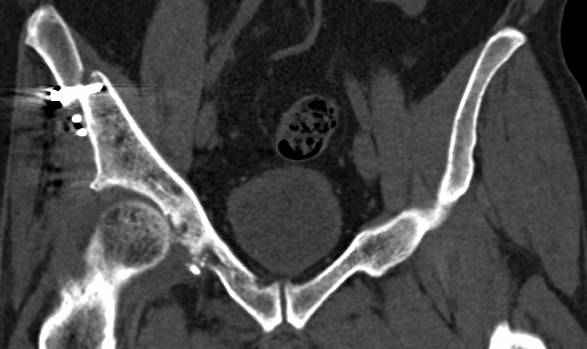

высылаю дополнительно сканы.

Когда перелом не получается отнести к какому либо типу - эффективнее всего описать более детально. В дальнейшем проще бывает сортировать, и что важнее - "руководство к действию" бывает более обоснованным. В данном случае графа клинического диагноза может выглядеть так: Застарелый разрыв правого крестцово-подвздошного сочленения, консолидирующиеся со смещением переломы крыла и тела правой подвздошной кости, обеих колонн и задней гемисферы правой вертлужной впадины. Состояние после остеосинтеза.

>Застарелый разрыв правого крестцово-подвздошного сочленения, консолидирующиеся со смещением переломы крыла и тела правой подвздошной кости, обеих колонн и задней гемисферы правой вертлужной впадины. Состояние после остеосинтеза.

По отдельным срезам и тем более по реконструкции трудно судить о сращении крыла и задней колонны с осевым скелетом.

В большинстве случаев при двухколонных переломах

в итоге получается прочный бублик с дыркой. При эндопротезировании в дырку помещается головка, а чашка должна неплохо заклиниться в бублике.

Главное, чтобы бублик не был разорван, что не очень понятно на представленных снимках.

Из того минимума, что представлено, мне кажется, мы имеем дело с двухколонным переломом вертлужной впадины. Обычно медиальный (центральный) "вывих" головки встречаются в сложных двухколонных переломах со смещением.

По-моему, надо готовить больного к будущей артропластике, но без опоры на задний столб невозможно удержать протез. Опорная конструкция (кольца и т.д.) должны иметь опору, и поэтому мы бы сделали реостеосинтез задним доступом. При надобности остеотомия и рутинная фиксация с межколонными винтами.